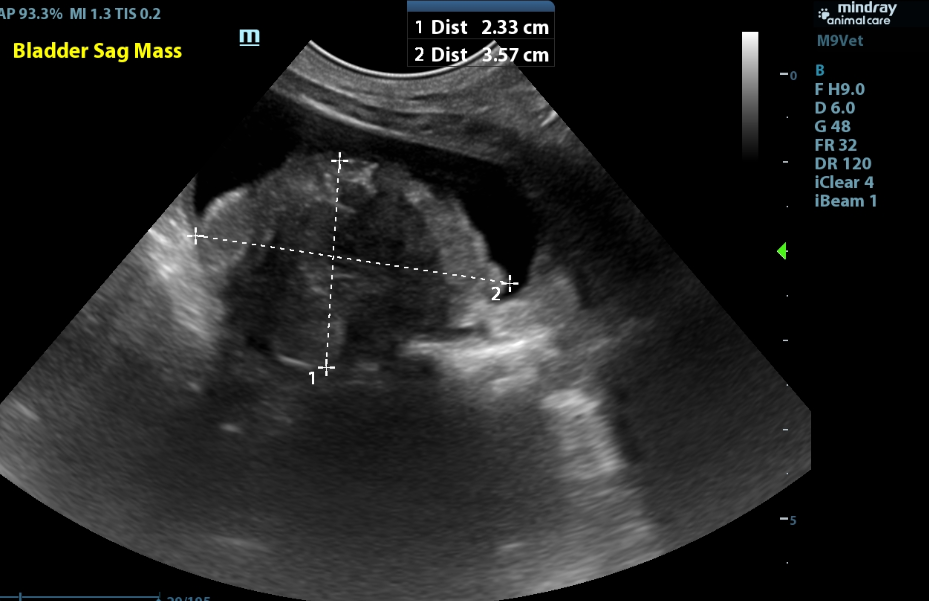

Bladder:

- The bladder is moderately distended with anechoic urine with a 2.3 x 3.6cm hyperechoic heterogenous mildly mineralized mass in the bladder that is sitting in the region of the trigone and occupying a moderate amount of space in the bladder lumen.